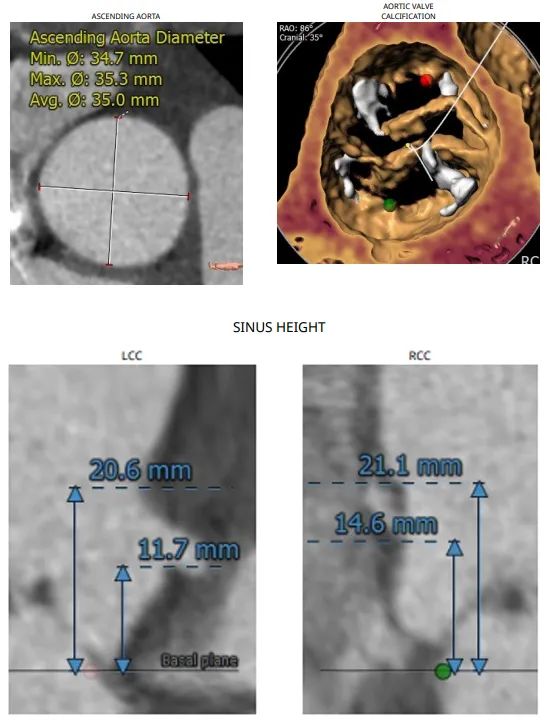

患者是一名70岁女性,门诊心脏超声提示患者有退行性心脏瓣膜病变、主动脉瓣重度狭窄、二尖瓣轻度反流、三尖瓣轻度反流、肺动脉高压、左室舒张功能减退、升主动脉增宽且既往有高血压病史。

第4例患者术前CT